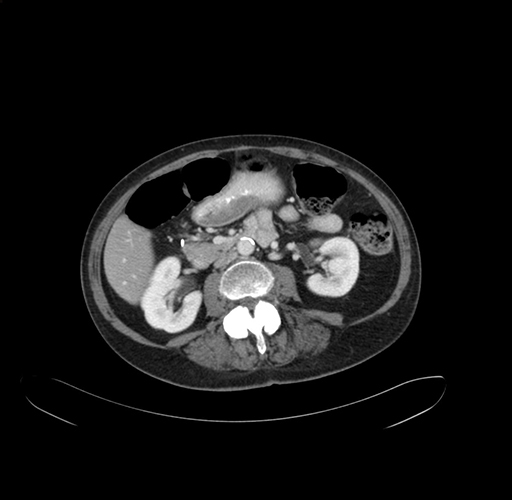

Pre-Chemo: Axial Venous

Imaging analysis

Based on your CT findings, which issue(s) would give reason for "planned slowing down moment(s)" in this case?

Considering a standard right hepatectomy procedure, what step(s) of the operation would you do differently in this case?